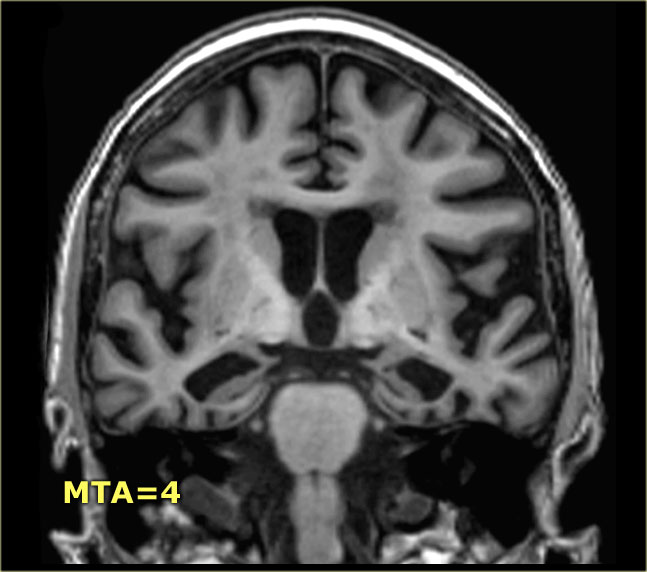

Điểm MTA cần được đánh giá trên chuỗi xung T1W mặt phẳng coronal tại một vị trí lát cắt nhất quán.

Chọn lát cắt qua thân hồi hải mã, ở mức cầu não trước.

Điểm số được tính dựa trên đánh giá trực quan chiều rộng của khe mạch mạc, chiều rộng của sừng thái dương và chiều cao của cấu trúc hồi hải mã.

- Điểm 0: Không có teo não

- Điểm 1: Chỉ giãn rộng khe mạch mạc

- Điểm 2: Kèm theo giãn rộng sừng thái dương của não thất bên

- Điểm 3: Mất thể tích hồi hải mã mức độ vừa (giảm chiều cao)

- Điểm 4: Mất thể tích hồi hải mã mức độ nặng

< 75 tuổi: Điểm từ 2 trở lên là bất thường.

> 75 tuổi: Điểm từ 3 trở lên là bất thường.

Tại đây bạn có thể cuộn qua các hình ảnh minh họa điểm MTA từ 0 đến 4.

Các dấu hiệu phù hợp với chẩn đoán AD giai đoạn cuối, vì có:

- Teo hồi hải mã và thùy thái dương trong mức độ nặng (điểm MTA: 4)

- Teo não toàn thể nặng nề (thang điểm GCA: 3)

Tuy nhiên, đây không phải là đặc hiệu cho AD, vì GCA nặng cũng xuất hiện trong các rối loạn giai đoạn cuối khác